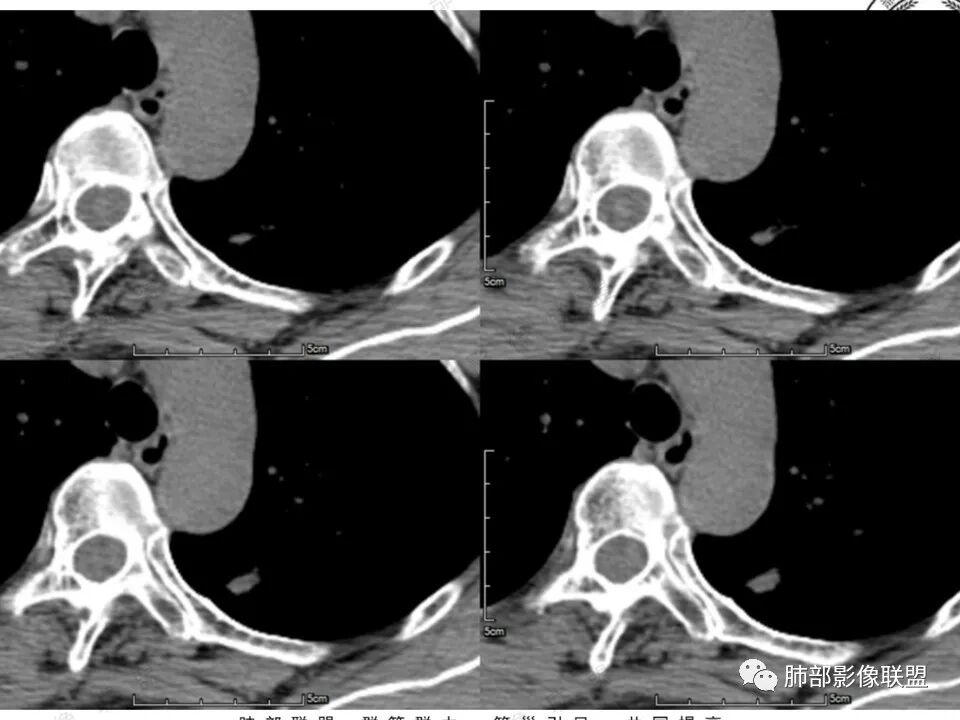

左肺上叶尖后段实性结节,边缘有清晰磨玻璃,胸膜有牵拉凹陷,明显强化,CT值超过主动脉,考虑血管畸形(周围磨玻璃可能是出血),鉴别IAC(影像表现符合,强化不符)

41岁女性,左肺上叶不规则结节,边缘见似清非清的磨玻璃影,叶间裂牵拉。整体病灶边缘平直,强化明显。另左上叶外侧尚有一磨玻璃结节(蘑菇兄弟?),考虑炎性肉芽肿可能性大。强化太明显让人很纠结,会不会存在CD,但边缘又有磨玻璃影;腺癌、结核、隐球都没有见过强化这么明显的,强化程度与主动脉基本一致,不会是动静脉畸形吧。

没意见:

强化太猛,血管畸形?边缘磨玻璃区,腺癌?

4.本例结节强化程度明显低于主动脉,也缺乏血管畸形的典型的迂曲结构,血管畸形可能性不大。